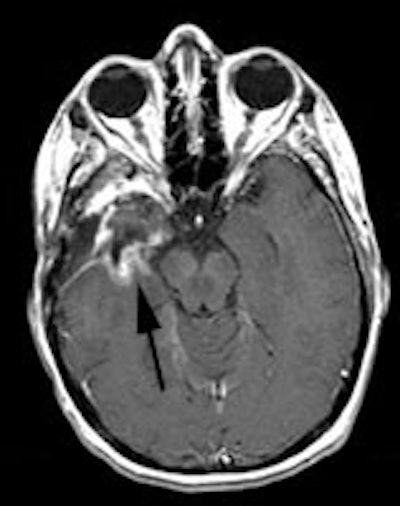

CNS radiation necrosis: The patient below had a history of a solitary brain metastasis from non-small cell lung cancer. The lesion had been resected and the patient had received radiation therapy to the area. A follow-up MR exam revealed a ring enhancing region in the left parietal-temporal area on post-gadolinium enhanced images (white arrows). A FDG PET exam revealed no tracer uptake consistent with post-surgical and post radiation change. |